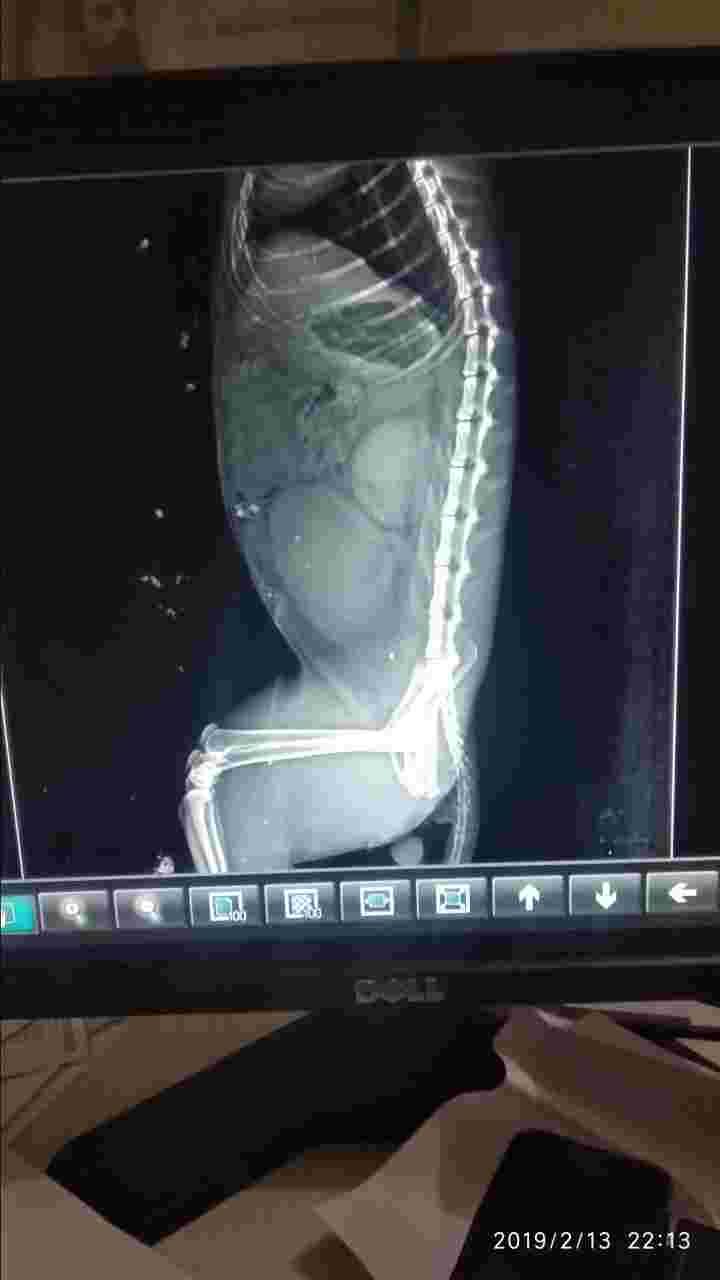

Pet's info: Cat | Persian | Male | unneutered | 3 years and 1 month old | 6.61 lbs

Actually my cat got a knot on his stomach...i was not knowing what happen to him..I took him to a vet and removed xray of it.vet doctor told me that "the knot on his stomach is from the cat food we were giving to the cat.Its meow cat food mackerel adult food.Because of that food my cat got knot on his stomach" thats why doctor told me to we will operate and remove taht knot..but after that operate my cat died.Please ill send you xray pictures..please tell me what was the exact problem to my cat.

I am so sorry for your loss! Without having seen Jack, there is no way I can tell you with 100% certainty what was wrong with him. From JUST looking at these x-rays, it looks like his bladder was blocked (unable to urinate) and there for his bladder got REALLY full and the urine eventually backed up into the kidneys. This likely caused him kidney values to increase and electrolytes to be abnormal. Unfortunately though, I cannot say this for sure and I have no idea if this is what caused him to pass away. I am sorry for your loss and please know you are in my thoughts.